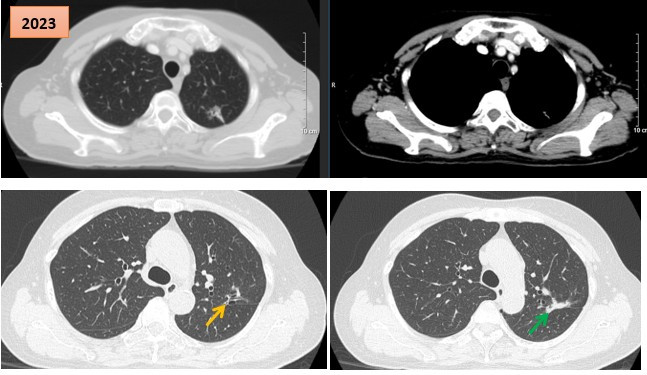

Lần đầu tiên, Bệnh viện Phổi Trung ương thực hiện hai ca ghép phổi trong một ngày

Thứ Tư, ngày 12/11/2025 06:07Chiều ngày 11/11/2025, Bệnh viện Phổi Trung ương tổ chức gặp mặt báo chí thông tin: Trong một ngày, Bệnh viện Phổi Trung ương đã phối hợp với các chuyên gia và các bệnh viện: Trung tâm Điều phối...